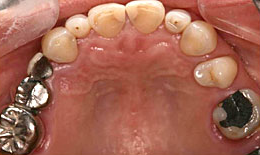

インプラント症例(9)女性 58歳

治療方法

- インプラントを6本埋め込んで、セラミックスクラウンを被せた